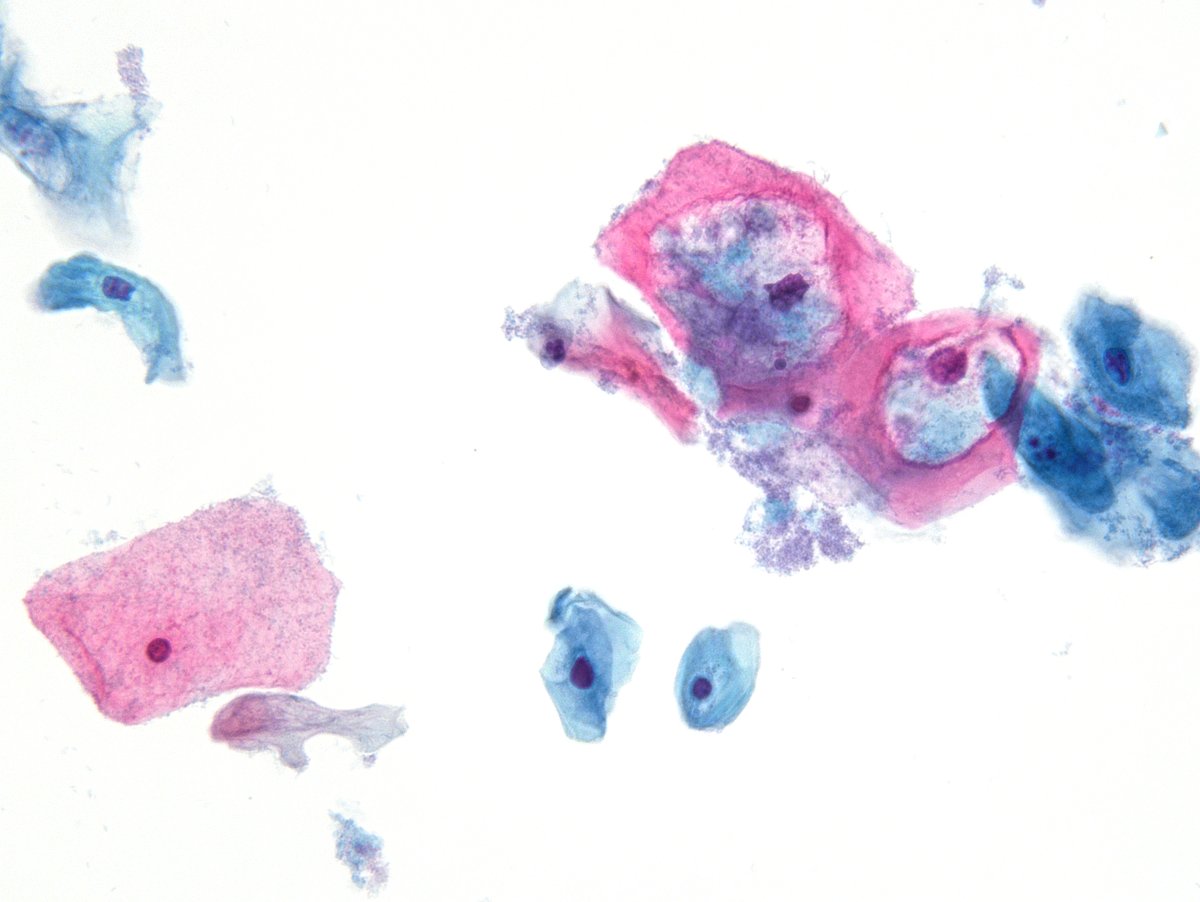

Endocervical adenocarcinoma in situ (AIS) Dr. Torous CCSP24 #pathology #pathologists #PathTwitter #PathX #pathresidents #pathfellow #cytopath #pathboards

Endocervical adenocarcinoma in situ (AIS)

Dr. Torous CCSP24 #pathology #pathologists #PathTwitter #PathX #pathresidents #pathfellow #cytopath #pathboards